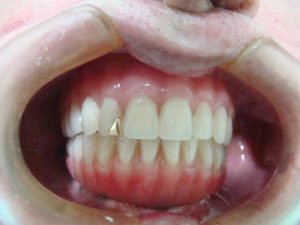

Veja os resultados de nossos pacientes

Encontre novamente seu prazer em saborear alimentos sem ter que se preocupar. Os implantes são totalmente firmes e não atrapalham no paladar como as dentaduras.

Seu Sorriso é seu maior canal de expressão, traga toda a alegria de volta para seu rosto e para sua vida. Invista no que é prioridade: Você mesmo!